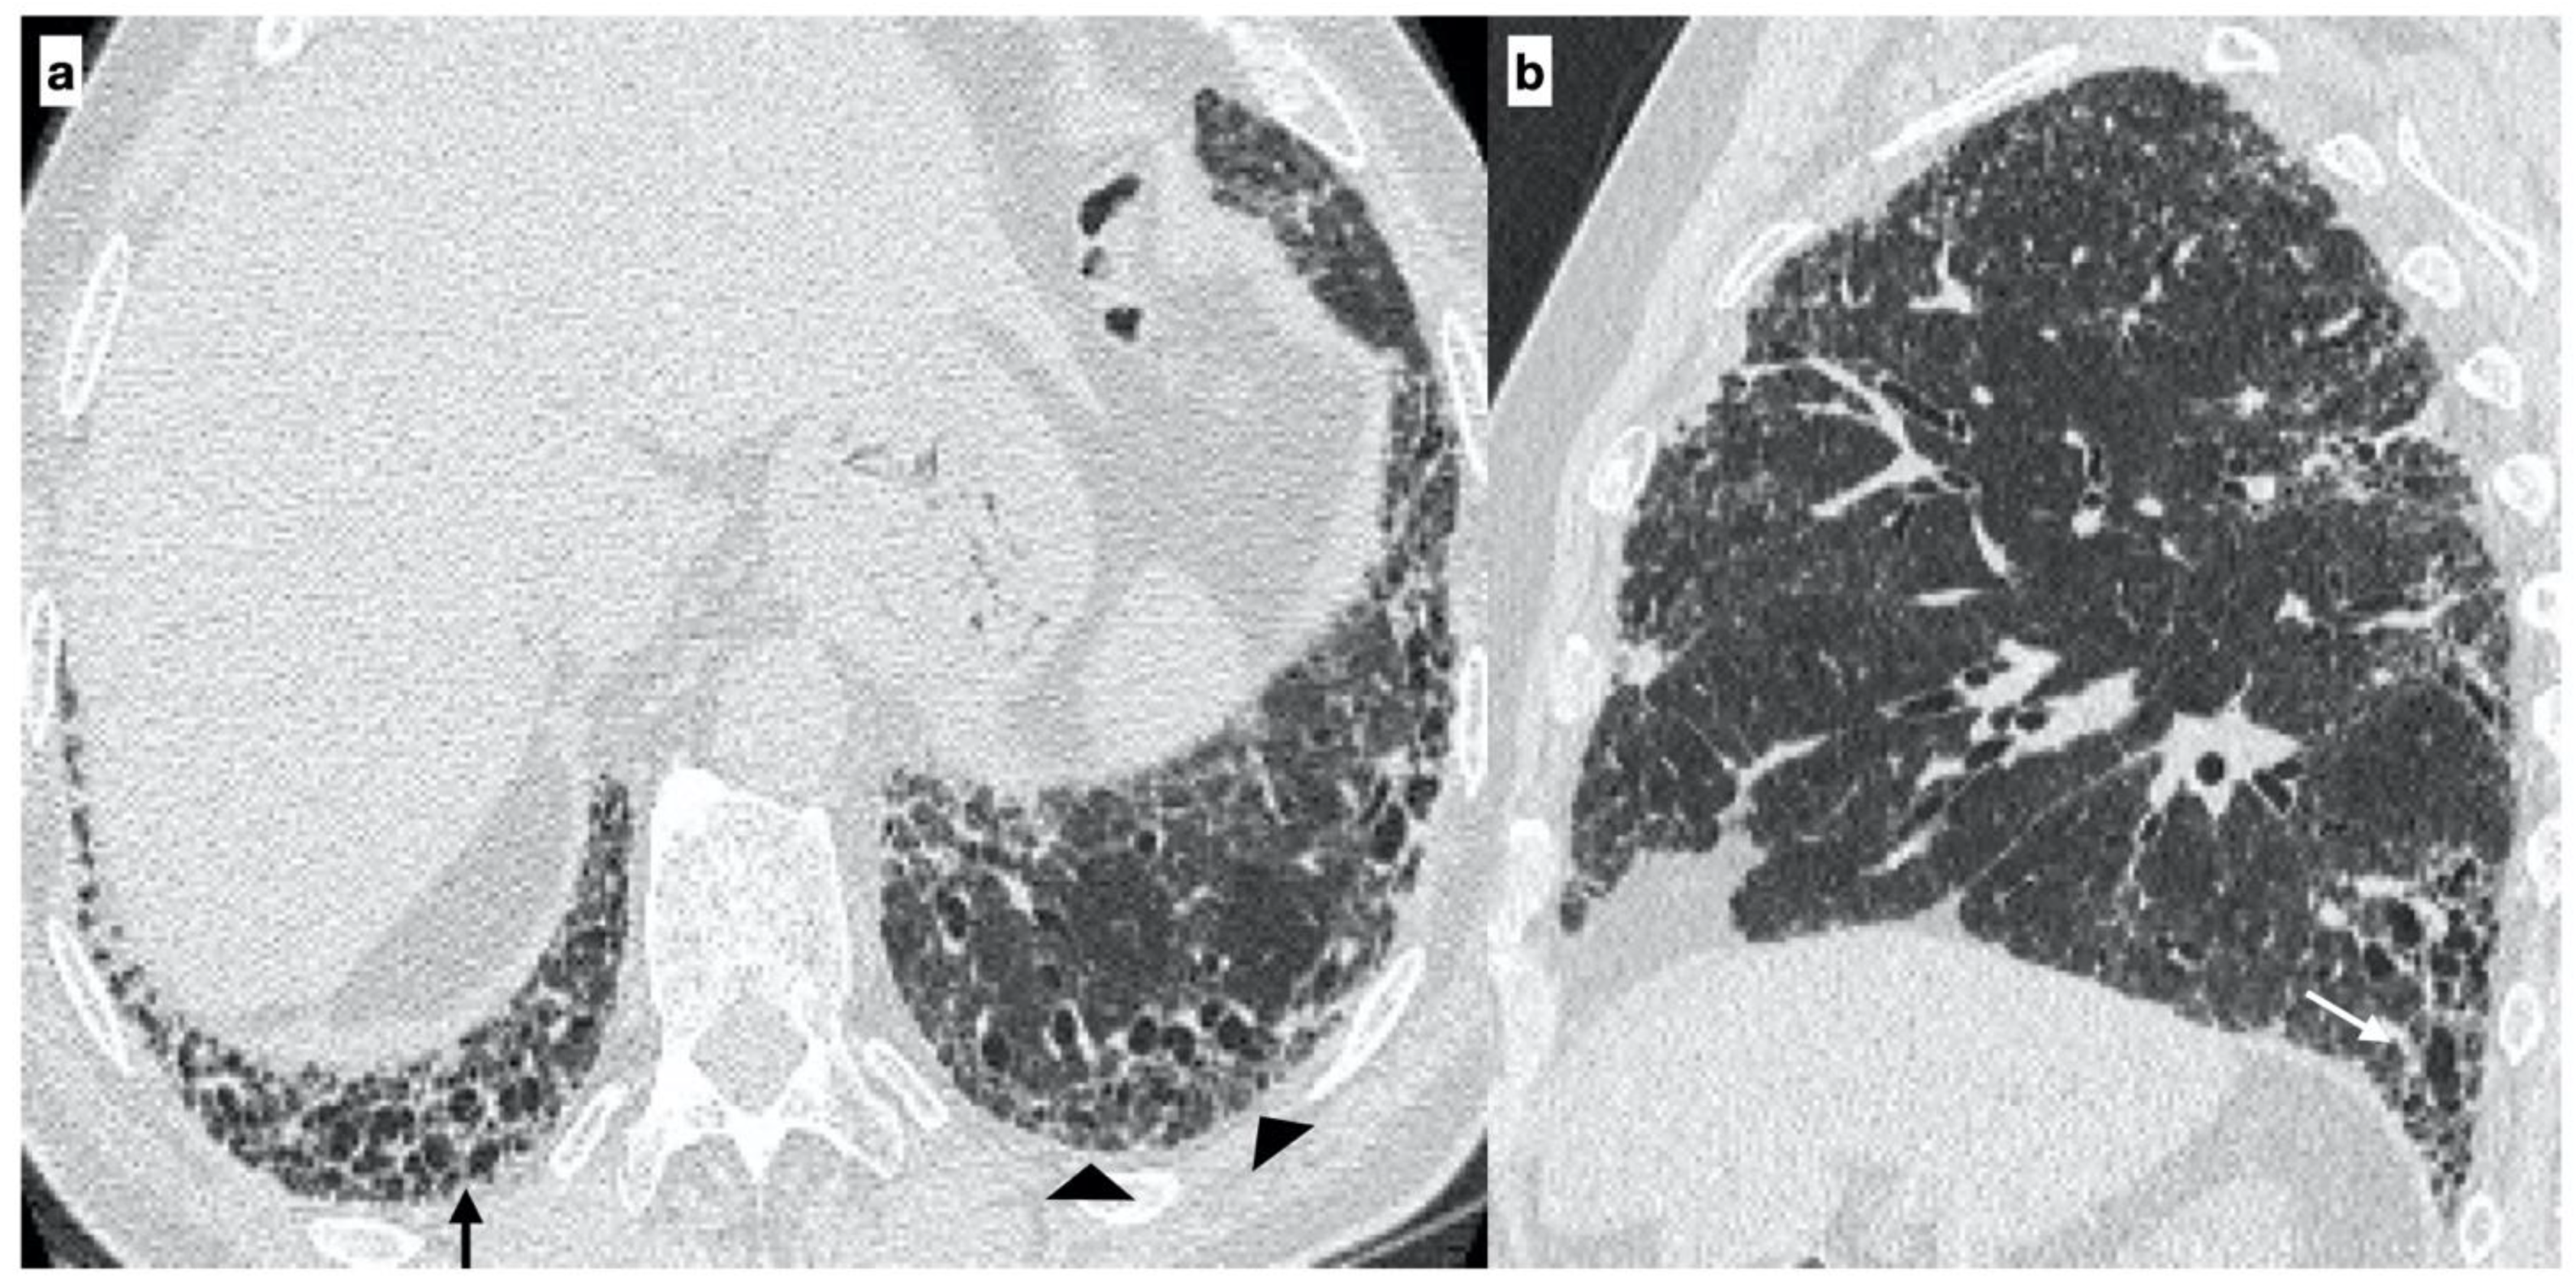

2.2. High-Resolution Computed Tomography

- Usual interstitial pneumonia (UIP): the presence of honeycombing in association with a reticular pattern with or without traction bronchiectasis/bronchiolectasis, with a subpleural and basal predominance;

- Probable UIP: the presence of a reticular pattern in association with traction bronchiectasis/bronchiolectasis without honeycombing and with a subpleural and basal predominance;

- Indeterminate UIP: the presence of subtle reticulation or ground-glass opacities, with a subpleural and basal predominance;